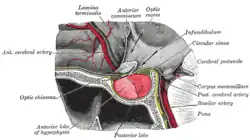

Die Hypophyse ist mit dem Hypothalamus über den Hypophysenstiel (Infundibulum) verbunden und wird in

eingeteilt. Entwicklungsgeschichtlich und funktionell unterscheiden sich die Hypophysenlappen voneinander. Während die Adenohypophyse aus einer Ausstülpung des Rachendaches, der sogenannten Rathke-Tasche, hervorgeht und sich der Neurohypophyse anlagert, ist die Neurohypophyse eine Ausstülpung des Zwischenhirns. Dieser Unterschied ist histologisch[2] zu erkennen, denn während in der Adenohypophyse verschiedene in Ballen angeordnete endokrine Drüsenzellen vorkommen, dominieren in der Neurohypophyse vor allem Nervenzellfortsätze, sogenannte Axone, deren Zellkörper im Hypothalamus liegen. Somit vermag die Adenohypophyse Hormone unter Kontrolle des Hypothalamus selbst zu bilden und die Neurohypophyse ist hingegen als Speicher- und Sekretionsorgan für die im Hypothalamus gebildeten Hormone zuständig. Aus Epithelresten des Stiels der Rathke-Tasche kann zusätzliches Vorderlappengewebe entstehen, das als Rachendachhypophyse bezeichnet wird.[3]

Die Hypophyse wird über vier Arterien mit Blut gespeist. Aus der Pars cavernosa der Arteria carotis interna entspringen zwei Arteriae hypophysiales inferiores, die vor allem im Bereich der Neurohypophyse ein Kapillarnetz bilden, in welches die entsprechenden Hormone abgegeben werden. Aus der Pars cerebralis der Arteria carotis interna entspringen zwei Arteriae hypophysiales superiores, die im Bereich der Eminentia mediana und des Hypophysenstiels Primärplexus bilden, in welchem einige Areale des Hypothalamus ihre Hormone, Liberine und Statine, sezernieren. Über die Venae portales hypophysiales gelangen sie in den Sekundärplexus, der an der Adenohypophyse liegt. In diesem Sekundärplexus gelangen die Hormone des Hypothalamus direkt an ihren Wirkort und es werden die Hormone der Adenohypophyse dort abgegeben, von wo aus sie in den Sinus cavernosus und damit in den Körperkreislauf abfließen, um ihre Wirkungen zu entfalten.